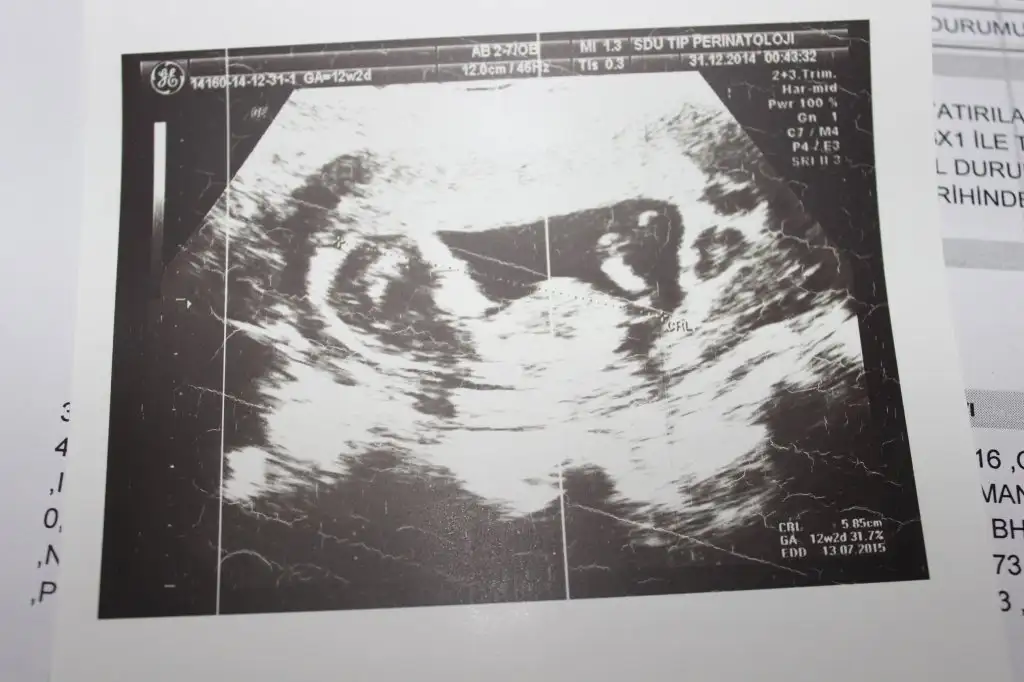

dr soylemeden siz gorun genital nub teorisi ( bebegin cinsiyeti)

IMG_1301.webp IMG_1302.webp IMG_1303.webp IMG_1306.webp

Kiz dedigim foto on haftalikmis zaten canm o haftada hepsi kiz gibi gorunur bilseydim kucuk derdim son fotodan belli erkek bebegin geliyor bence

arkadaşlar bana kız diyende var erkek diyende benim bebeğim belli etmiyomu yaa bnde anlayaadım ne paralel ne yukarı dogru :D